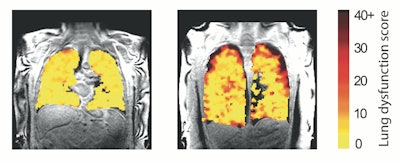

"In those with chronic rejection, the scans showed poorer movement of air to the edges of the lungs, most likely due to damage in the very small breathing tubes (airways) in the lung," they wrote.

Lung function MRI showing problem areas (measurement levels of dysfunction) in lung transplant recipients.Image and caption courtesy of Newcastle University in Newcastle on Tyne, U.K.